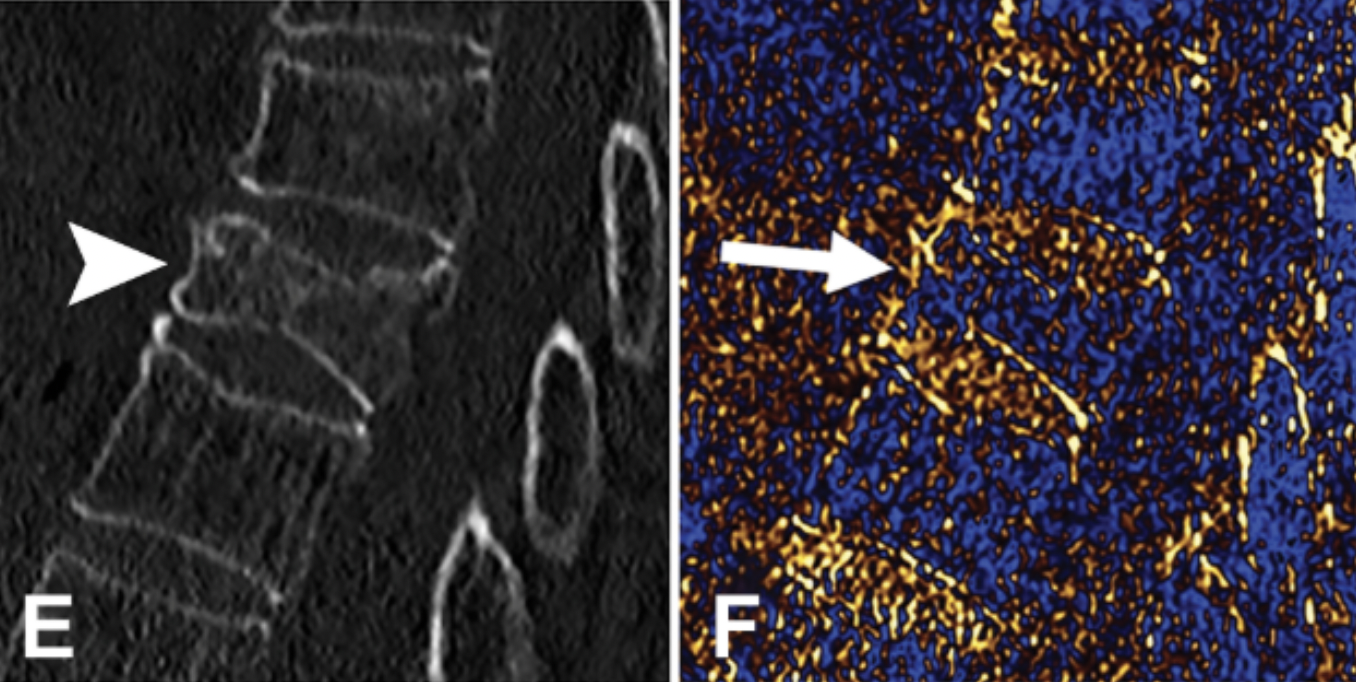

• Material decomposition algorithms can also be used to create additional images (for example, removing the contribution of iodine to produce virtual noncontrast images, or removing the contribution of calcium for bone removal).